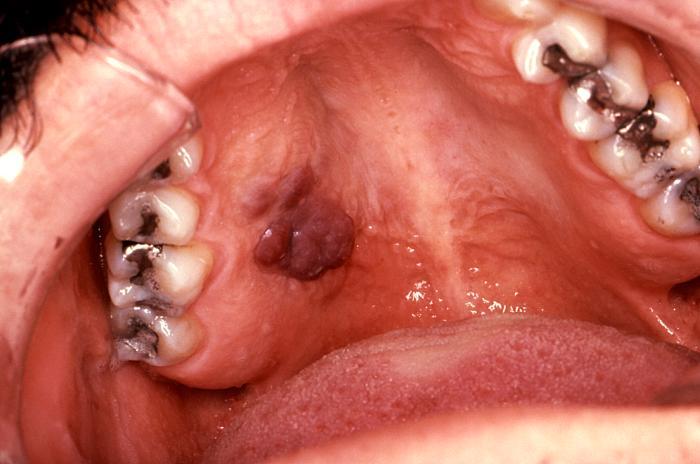

KS mucosal lesion

Intraoral KS in patient with AIDS. About 10% of patients with advanced AIDS will have mucosal lesions of KS. Lesions may be small to larger, nodular growths.

Source: CDC, S. Silverman DDS San Francisco